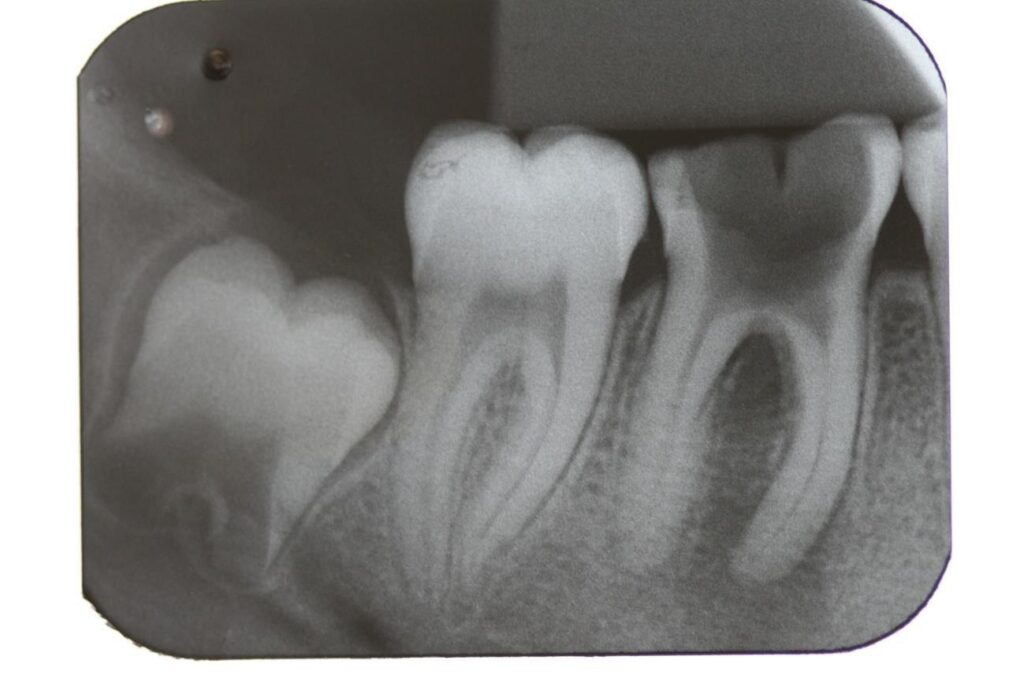

Paciente, sexo feminino, 15 anos de idade compareceu a clinica Consult Odontologia, em Tucuruí-PA, com histórico de perca precoce do primeiro molar inferior direito (dente 46). Ao exame clínico, observou-se presença de destruição coronária e desarmonia oclusal. Através de uma radiografia periapical, confirmou-se o diagnóstico de necrose pulpar com comprometimento da estrutura dentária, com rarefação óssea indicando lesão periapical no dente em questão (figura 1).

Figura 1 – radiografia de diagnóstico